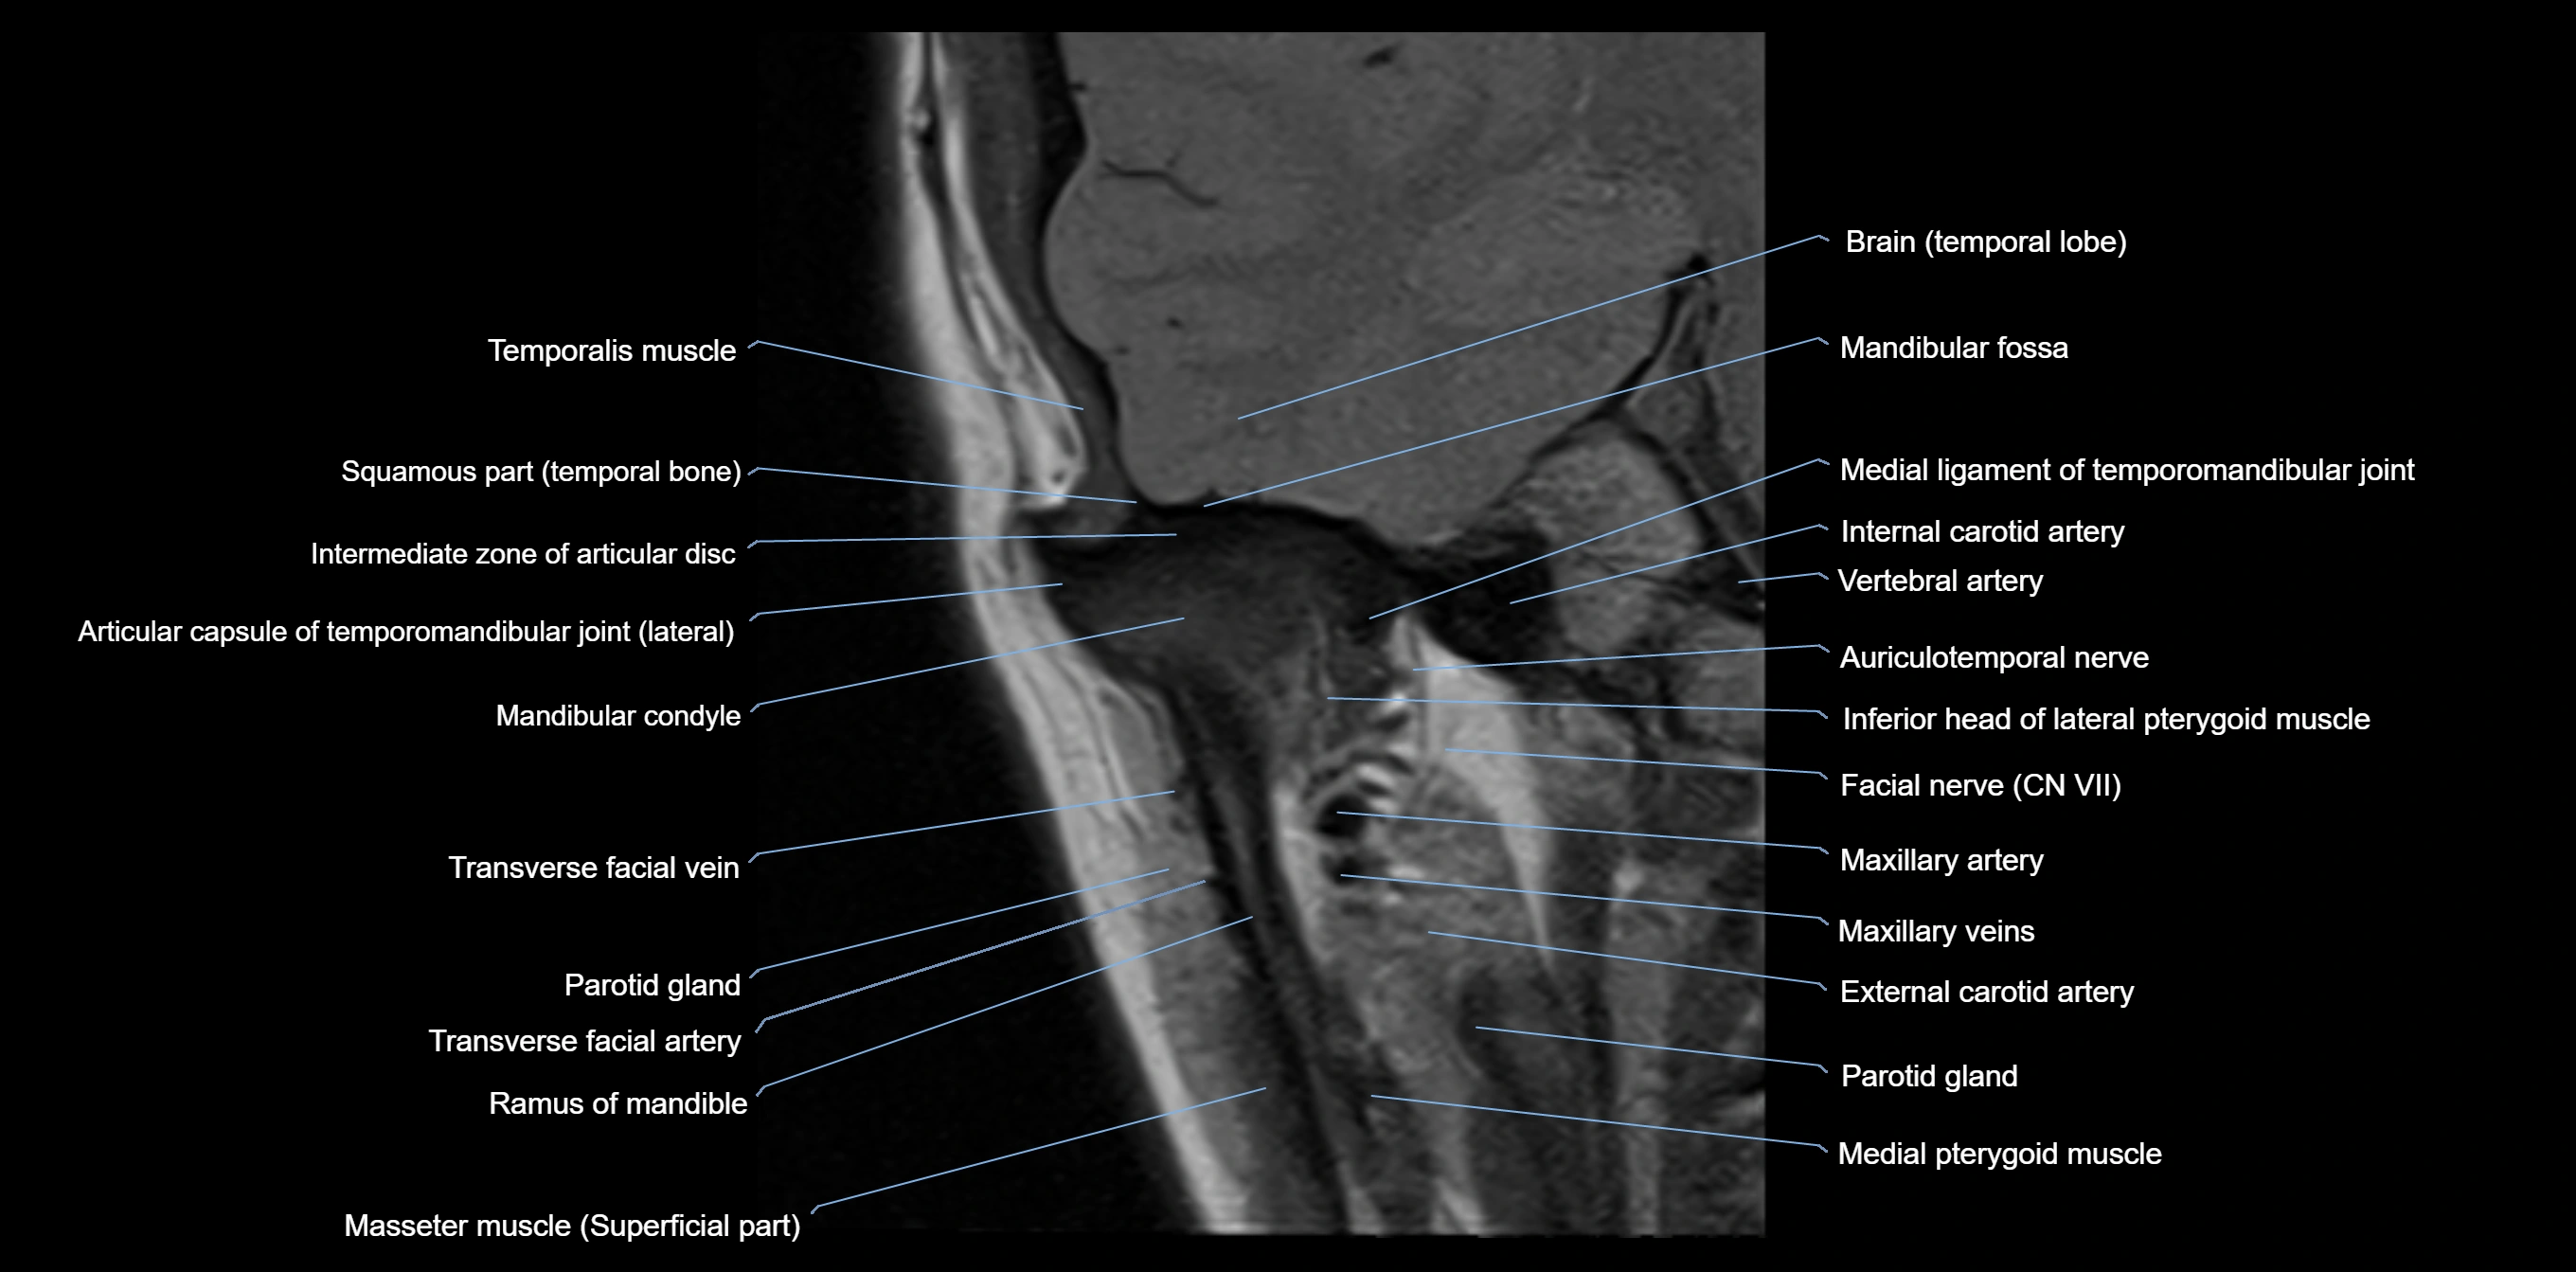

MRI appearance

T1-weighted images:

• Cortical bone: Low signal intensity

• Cancellous marrow: Intermediate to high signal depending on fatty content

• Teeth: Signal void structures

• Adjacent soft tissues: Normal gingiva and oral mucosa signal

T2-weighted images:

• Cortical bone and teeth: Low signal

• Marrow: Intermediate signal